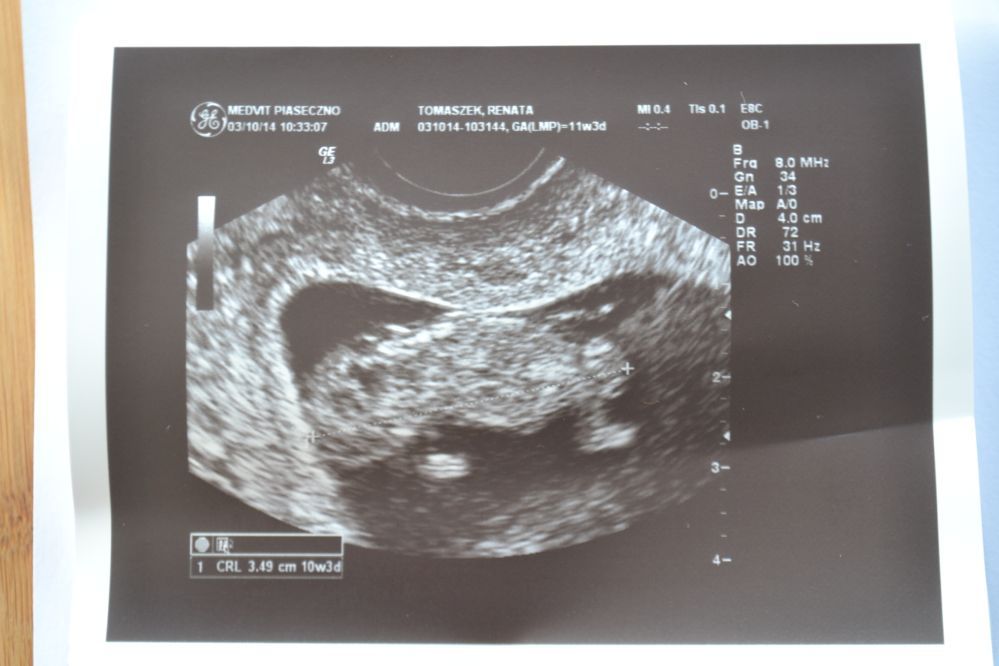

Jutro wkleję dwa zaległe zdjęcia i może trzecie świeże